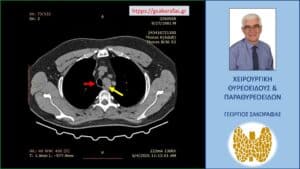

Αξονική τομογραφία – εικόνα σε διατομή κατά το προσθιοπίσθιο επίπεδο. Και στη διατομή αυτή φαίνεται η βαθιά κατάδυση του αριστερού λοβού (κίτρινο βέλος), που φθάνει στο άνω όριο του αορτικού τόξου (πράσινο βέλος).